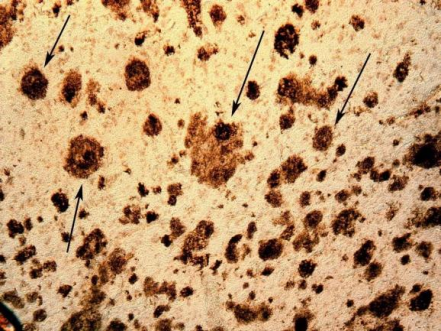

(箭头:淀粉样斑块)

正常情况下,神经细胞产生低浓度 Aß,Aß来源于淀粉样前体蛋白 (amyloid precursor protein,APP) 的水解。APP 的分解途径有“分泌酶分解途径”和“溶酶体分解途径”[3],分泌酶分解途径发生在细胞膜表面,共有 3 条途径,分别由分泌酶 a、ß、y 作用完成。AßPP 是一种跨膜糖蛋白,正常情况下被 a 分泌酶水解,生成可溶性分泌型 APP(sAßPP),sAßPP 可由组织正常分泌,它可以刺激细胞增殖、促进细胞间和基质的黏附,保护神经元免受兴奋性毒素和氧化反应损伤。ß和 y 分泌酶可分别在细胞膜外或跨膜部分将 AßPP 水解成一完整长度的可溶性 A,溶解状 AßPP 通过 G 蛋白干预细胞内信号过程,增加微管相关蛋白激酶的活性。不同因素都可以影响 AßPP 的水解方式。通过调节 AßPP 的 3 条途径,如增加 a 分泌酶的活性、减少ß和 y 分泌酶途径,可以减轻 Aß神经毒性作用。此外,发生 APP 基因突变及过表达时,可以扰乱自身的调节机制,当 APP 表达超过其正常途径的代谢能力时,可导至 APP 通过其他途径如溶酶体途径分解,产生大量 Aß,脑间质进行性堆积不溶解的 Aß沉积形成弥散斑块 [4] 从而在 AD 形成的病理过程中发挥作用。Aß能自发快速聚集形成ß- 片层折叠结构,进而形成纤维沉积导至 SP 发生,所以 Aß是 SP 的核心物质。一般认为 Aß浓度过高、ß折叠和纤维形成是具有神经毒性作用的基础。